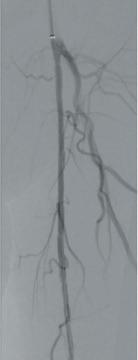

Here, we present a case of a severely limited claudicant who presented with three years of worsening calf pain. The patient was a prior smoker who was treated with maximum medical therapy and a walking program. This initially improved the symptoms, but after three months she regressed. Exercise anklebrachial indices (ABIs) were performed. At rest, the ABI on the left leg was 0.67. With exercise this decreased to 0.17. On the angiogram, there was a long segment stenosis of the superficial artery (SFA), but otherwise there were threevessel runoffs to the foot (see figure 1). Pre-intervention IVUS was used to size the diameter of the SFA through the long segment of diseased artery. Predilatation was performed followed by

the Stellarex drug-coated balloon (DCB). Completion arteriogram showed marked improvement in flow but a possible dissection in the mid-segment of the SFA. IVUS’ unique ChromaFlo feature was then used to identify and confirm the areas of dissection (see figure 2) Most of the vessel had significant luminal gain but there were multiple areas of short-segment dissection. These were then treated with placement of a total of six Tack Endovascular System implants. The Tack implants were then post-dilated using plain old balloon angioplasty (POBA). Completion angiogram and IVUS (see figure 3) demonstrated resolution of the dissections. Follow-up ABI was 0.95 at rest.